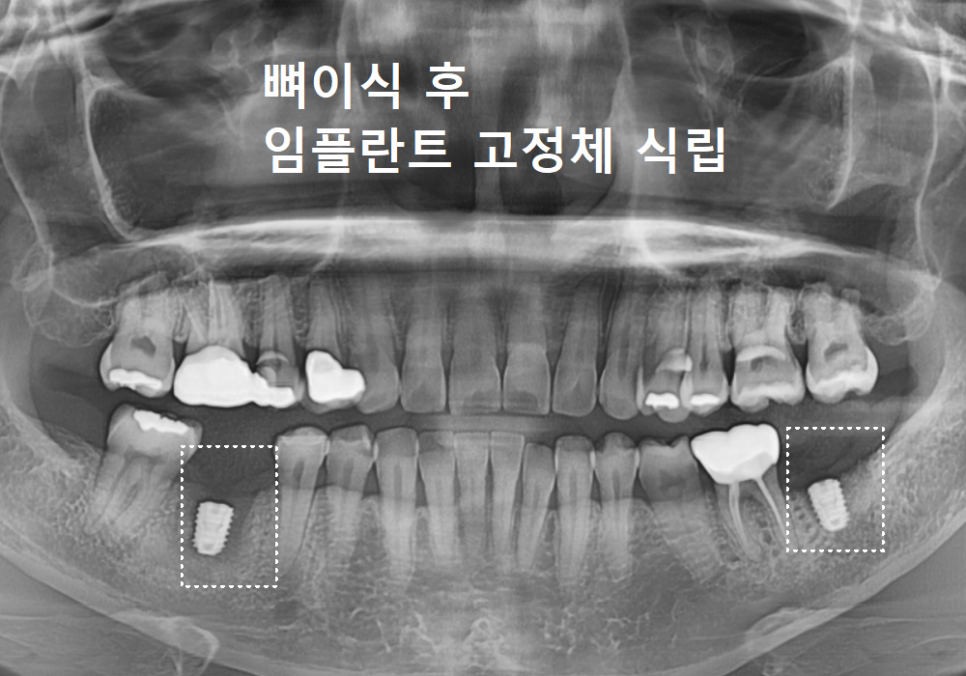

이 환자분도 뼈이식 후

약 3개월 정도 충분히 기다린 뒤,

뼈가 형성된 것을 확인하고

임플란트 뿌리를 심었습니다.

250620